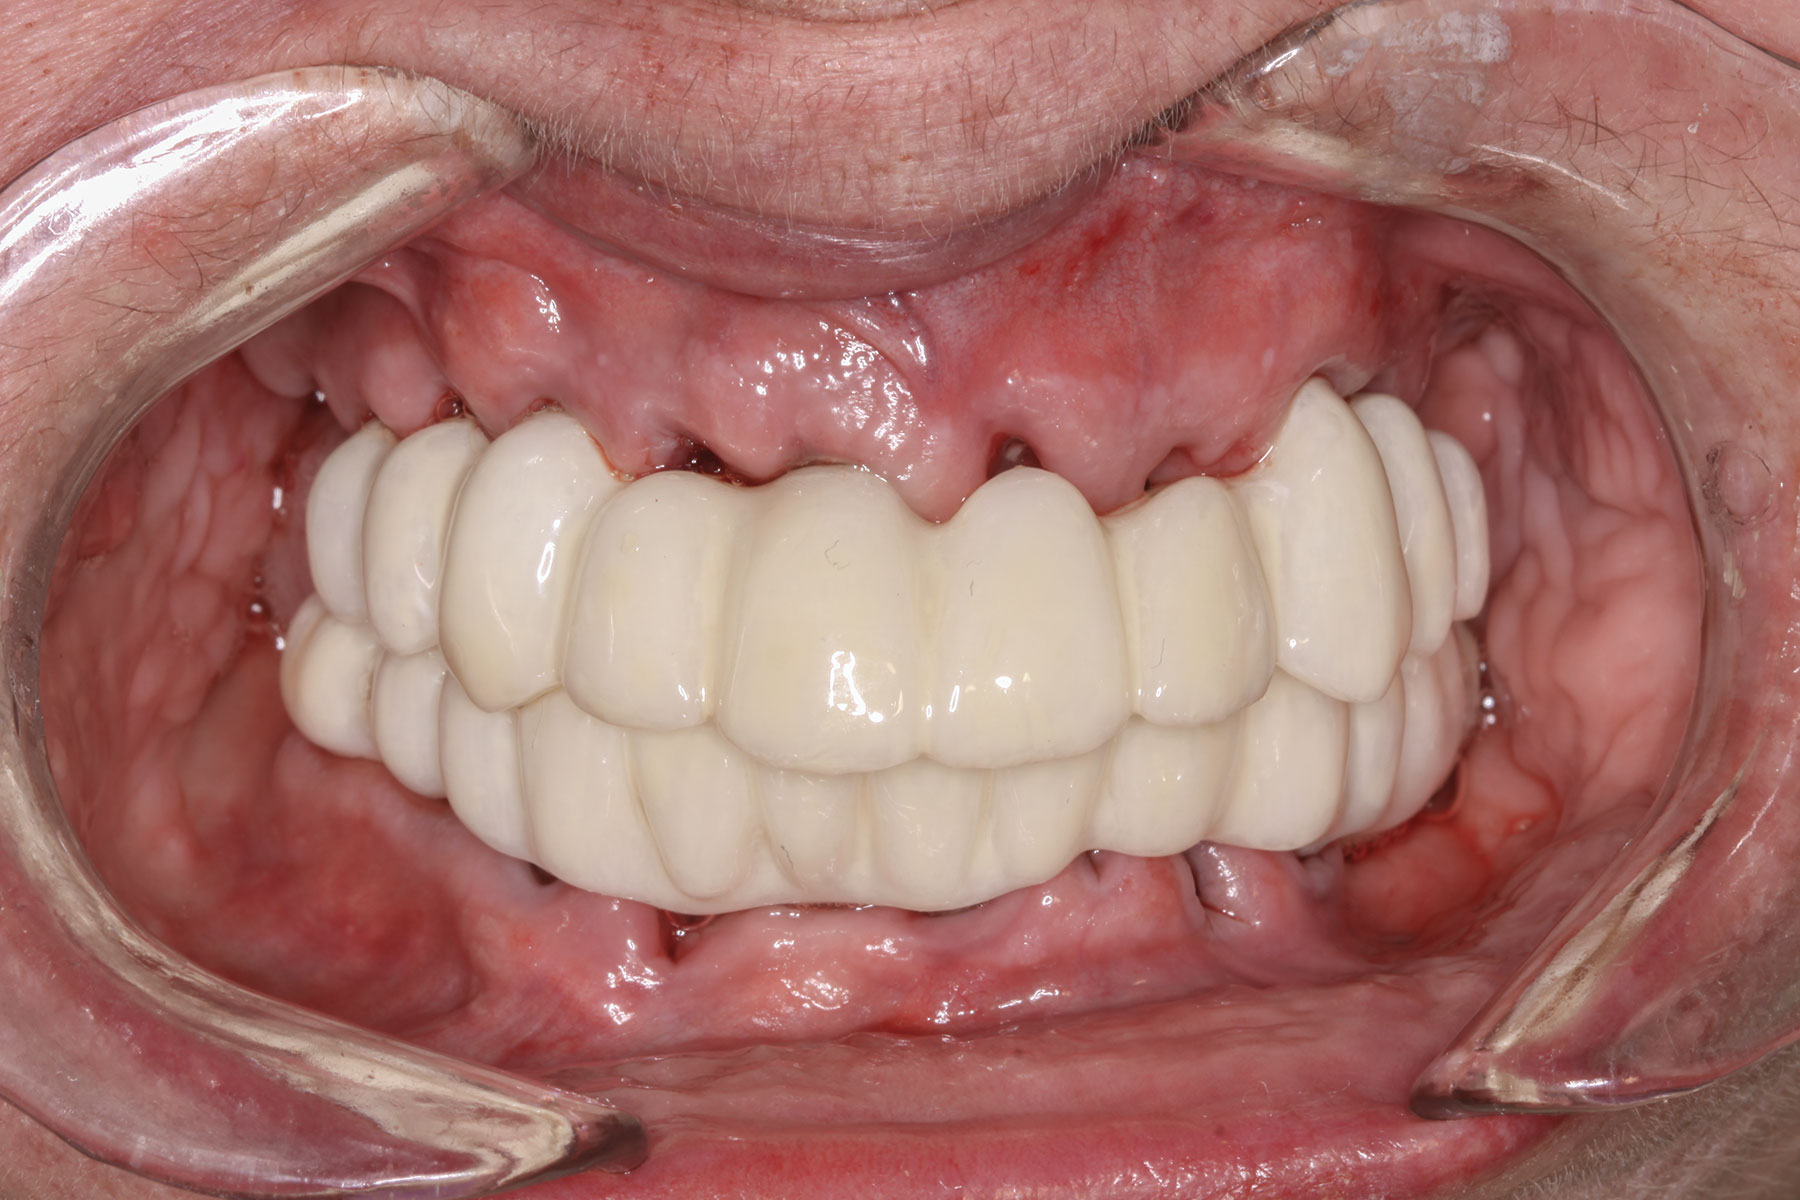

Case 3

A 67-year-old female patient presented with a highly compromised maxillary and mandibular dentition, including teeth Nos. 2 through 15, 17, 21 through 24, and 27 through 30. Soft tissues were of normal contour, and bone profiles were generally sustained and favorable. The patient was excited about the prospect of transforming both her maxillary and mandibular compromised esthetics and function in one visit. (Case 3 is depicted in Figure 23 through Figure 42.)

This file was then electronically returned to the dental team via the proprietary web portal. The office staff then sent the STL design file to the practice's 3D printer software, and the appropriate color nanoceramic resin was used to print the prosthesis at 100 microns. Once this was accomplished, the prosthesis was stained and glazed and gingival color was applied to establish optimum esthetics.

The completed prosthesis was then screwed directly onto the multi-unit abutments with Rosen screws with no ti-bases and torqued to 20 Ncm. Screw-access holes were filled, and no occlusal adjustment was necessary. The fit of the prosthesis was precise and stable and the phonetics of the patient was ideal. The patient was overwhelmed by the significant esthetic improvement with this set of teeth in place.